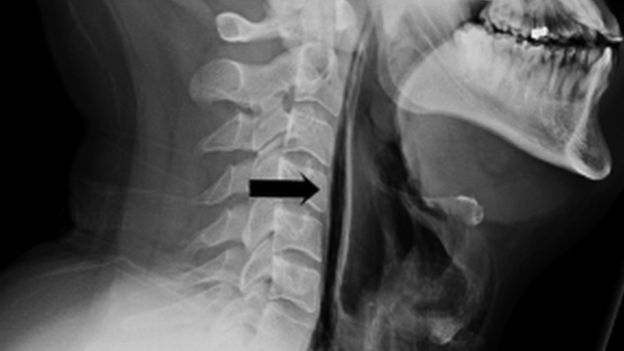

くしゃみを我慢した直後に、声の異変や飲み込みに不自由を感じるようになった男性は病院へ。そこで医者から「喉が破裂している」ことを知らされたという。男性いわく、くしゃみを感じた瞬間首に一瞬の衝撃が走ったそう。どうやらそれは、喉が破裂したことが原因だったようだ。こちらがそのレントゲン写真。

©BMJ Reports